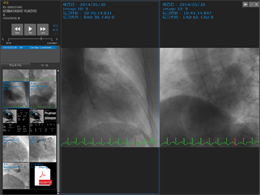

- Bi-Plane同期再生

- ECG(心電図)同期表示

検査画像の中からペアになる画像を自動検出し、2分割表示します。